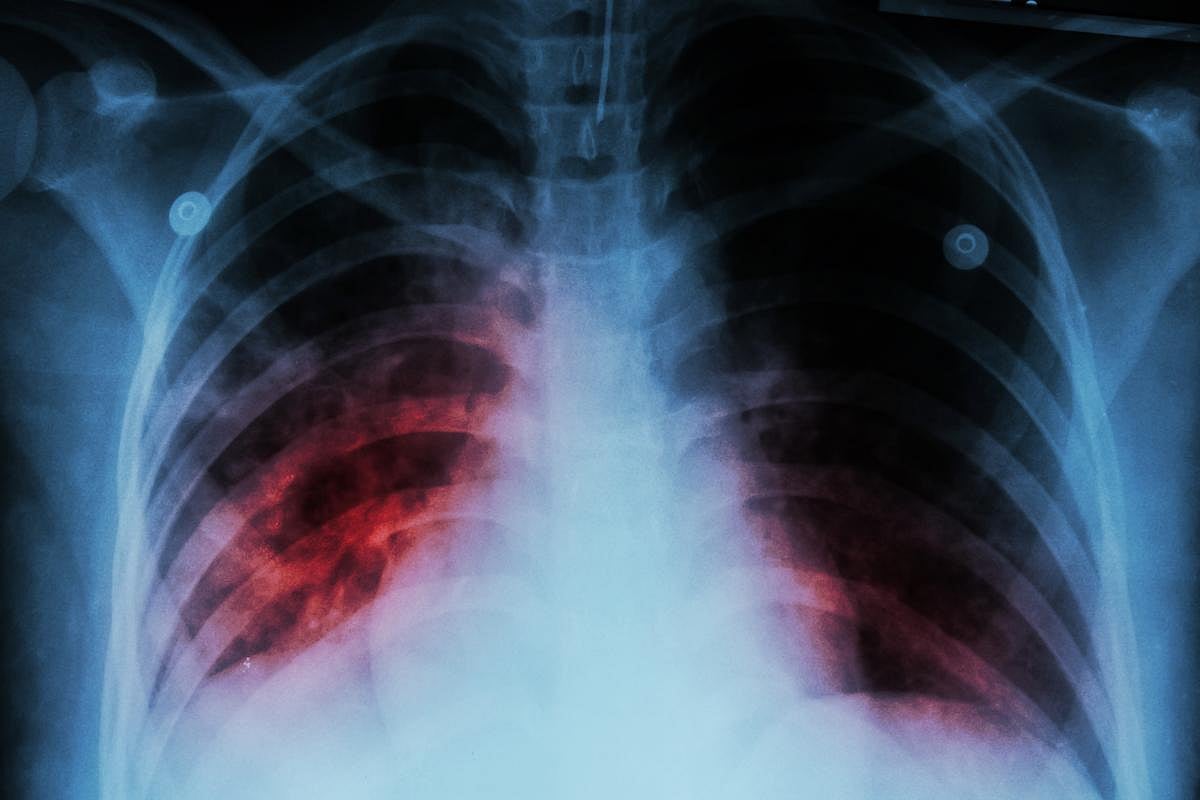

Tuberculosis is caused by airborne bacteria that mostly attacks the lungs. Roughly a quarter of the global population is estimated to have TB, but only about 5% to 10% of those develop symptoms, the WHO said.

The symptoms people get depend on which part of the body is affected by TB. While it typically strikes the lungs, it can also damage the kidneys, brain, spine and skin, the WHO added.